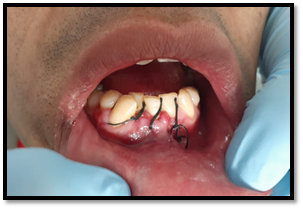

Paciente de sexo masculino de 32 años de edad, Asintomático, en la exploración clínica intraoral se observa ausencia del órgano dentario Nº 4, 2. No hay la presencia de cambios de coloración en la mucosa del sector anterior del cuerpo de la mandíbula, a la palpación no refiere dolor.

Imagen 1. Fotografías intraorales